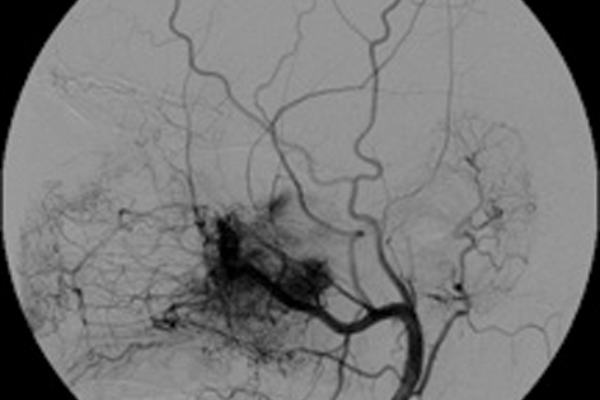

Role of interventional neuroradiology in otorhinolarygological pathology – a brief review